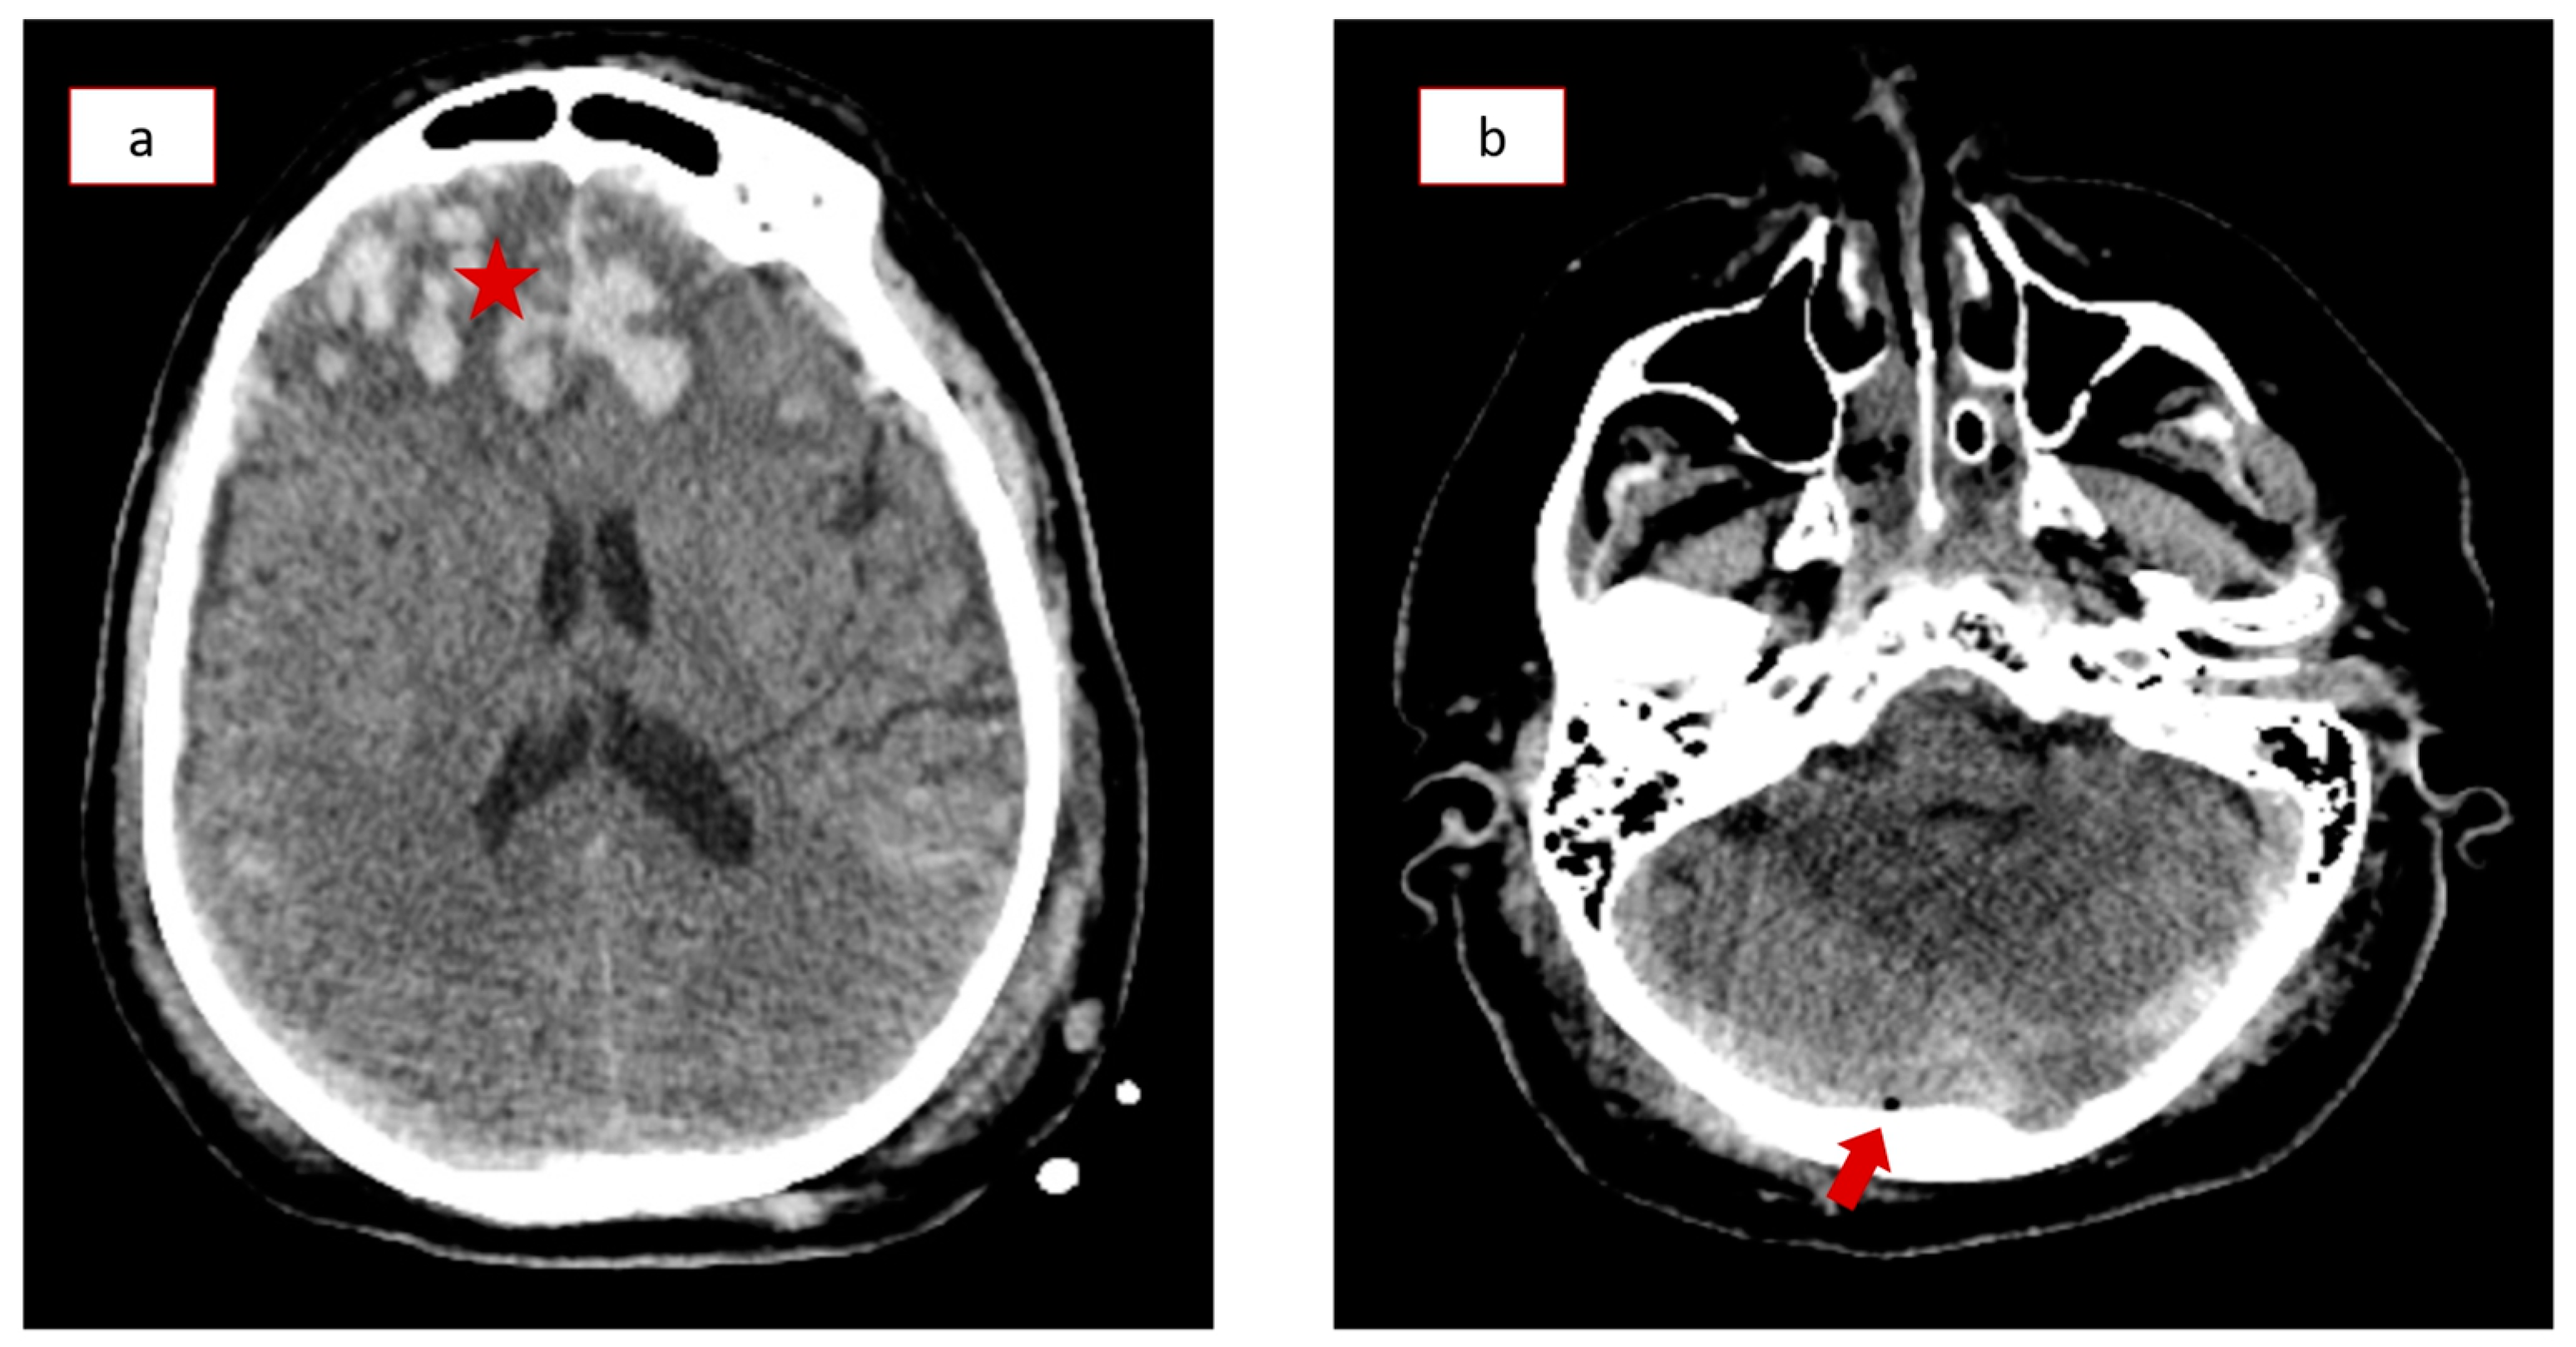

2. Case Presentation

3.4. Diagnosis and Radiological Findings